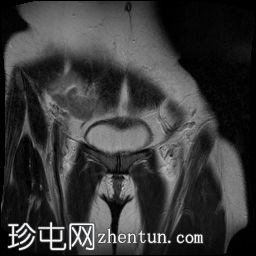

矢状位

T2加权像

子宫增大且体积较大。扩张的血管主要位于子宫后壁(符合子宫动静脉畸形)。

子宫内膜肌层交界处也存在异常。

子宫内膜腔显影清晰,外观正常。